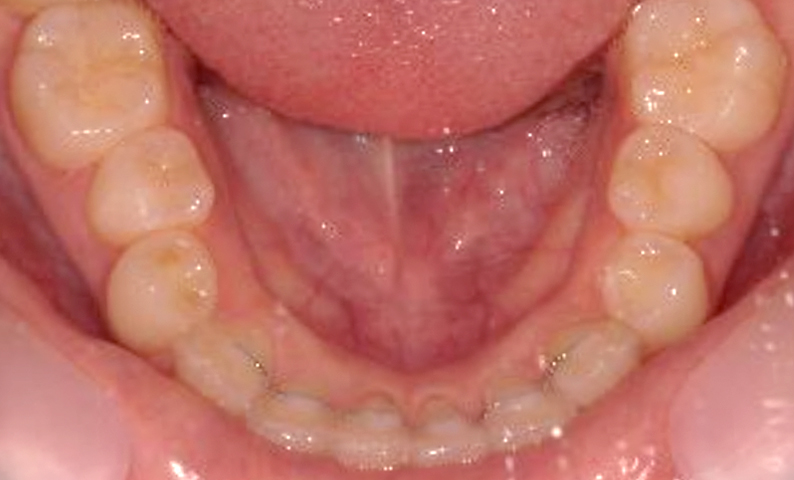

症例_001 上下顎の部分矯正

治療期間:12ヶ月金額:54万円+税女性前歯のガタガタ逆八の字